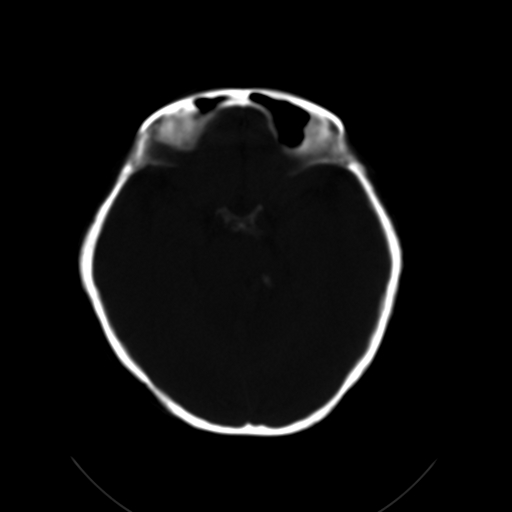

标题: CL0976:颅骨凹陷征 [打印本页]

标题: CL0976:颅骨凹陷征

女,56岁,头痛,没有其他的神经系统的阳性体征

颅底陷入是枕大孔周围骨,包括枕骨基底部、髁部和鳞部上升向颅腔内陷入的畸形。环、枢椎也随之上升、突入。多属枕骨及环枢椎先天性发育异常,也可继发于引起颅底软化的疾病、成骨不全或佝偻病等。

颅底凹陷症!这样横断位未见过,平时都是颈椎侧片所示。建议颈椎mr检查。

颅底凹陷.典型.